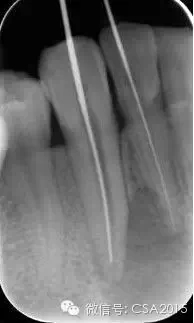

3 確定根管工作長(zhǎng)度

應(yīng)用平行投照X線方法、根管長(zhǎng)度測(cè)量?jī)x確定根管度,最好插針拍X片